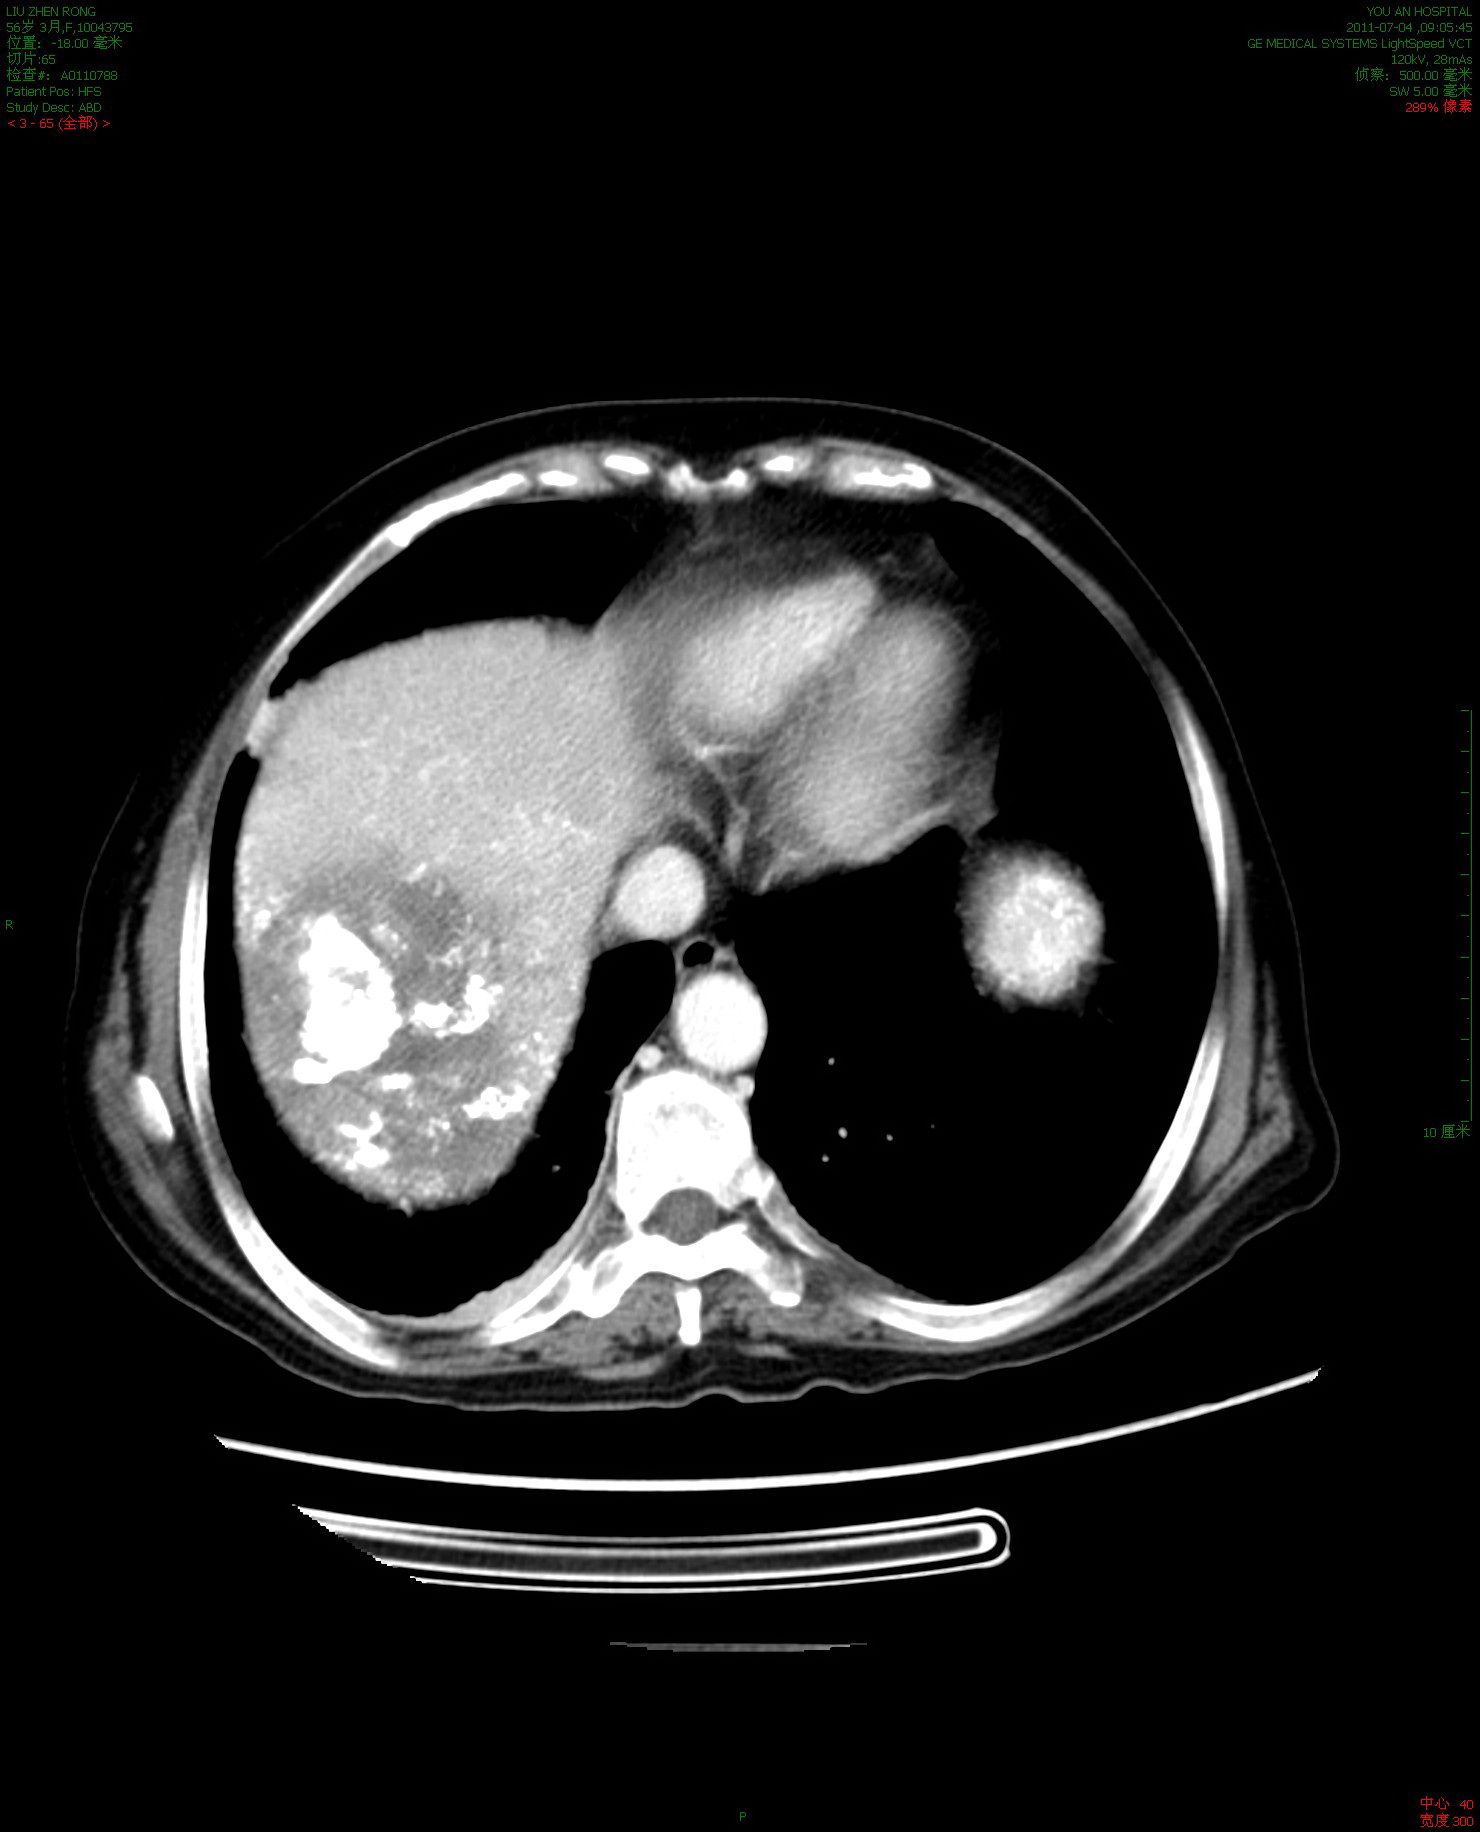

肝愿同行丨晚期肝癌伴肺转移治疗棘手免疫靶向强强联手3周期后疗效pr

图片尺寸788x576